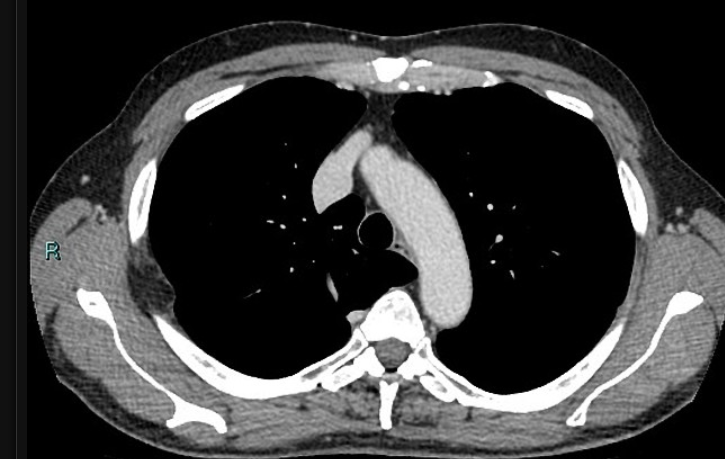

70 anos, masculino

Disfagia.

Leiomioma do esôfago

Neoplasias benignas do esôfago são raras (<1% dos tumores do esôfago)

TC: Massa intramural, bem definida, circunscrita, arredondada; densidade de partes moles; calcificação é quase patognomônico; realce difuso discreto / moderado pelo contraste.

Tumores pequenos < 5 cm geralmente são assintomáticos; tumores maiores podem causar disfagia, obstrução, tosse e sangramento.